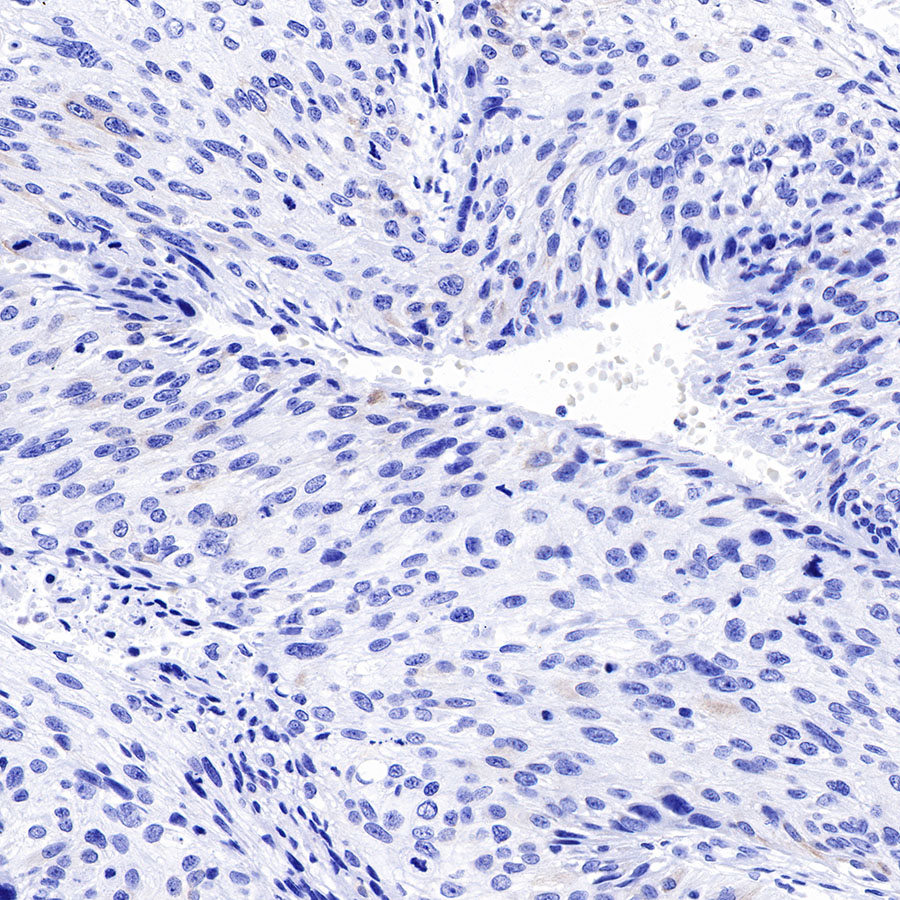

| IHC-P |

1:2000 |

Cytokeratins are proteins of cytoskeletal intermediate filaments, and their main function is to enable cells to withstand mechanical stress. In humans, 20 different cytokeratin isotypes have been identified. Cytokeratins 8, 18, 19, and 20 have been associated with bladder. Cytokeratin 18 (KRT18, also called K18), found in epithelial cells, is released from hepatocytes upon death.